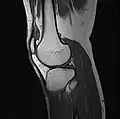

MRI

Both anterior cruciate ligament (ACL) and posterior cruciate ligaments (PCL) are hypointense on both T1 and T2 weighted images of MRI. However, some high signal striations are often seen at the distal part of the ACL, making ACL higher intensity than PCL on MRI scans.[20]

-

Knee MRI (PD TSE FS sagittal) -

Knee MRI (T1 TSE sagittal) -

Knee MRI (sagittal TSE FS)